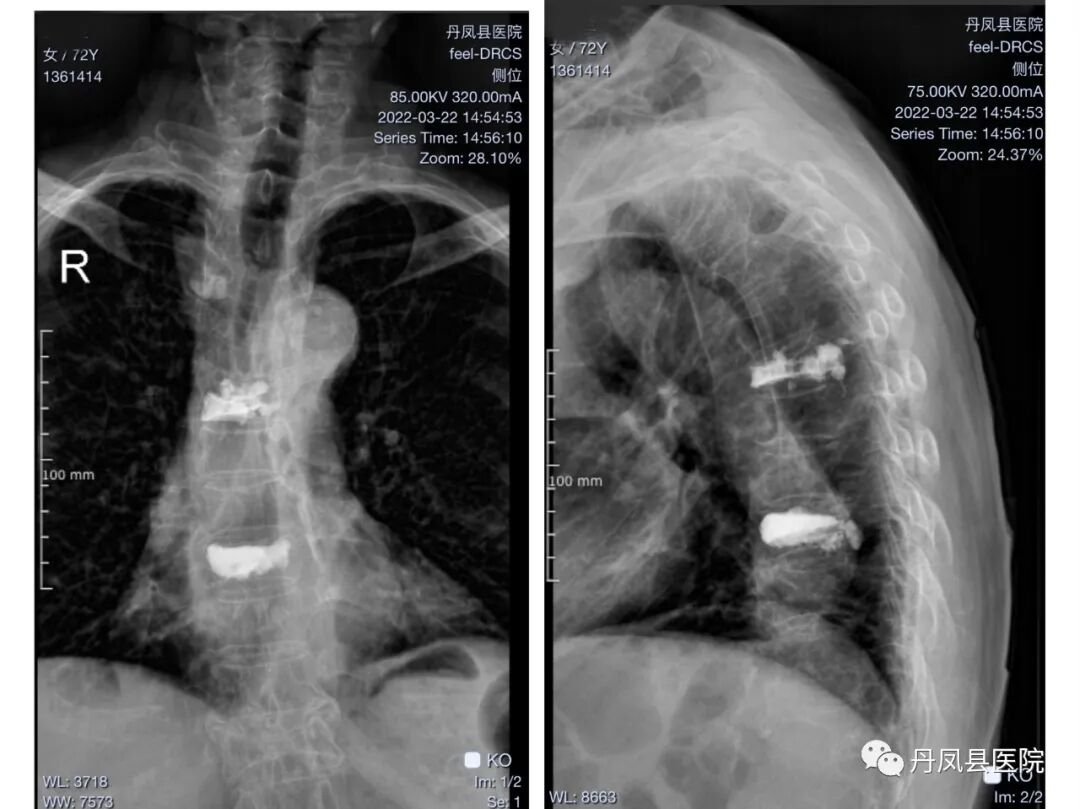

图为患者术前胸椎影像图片![]()